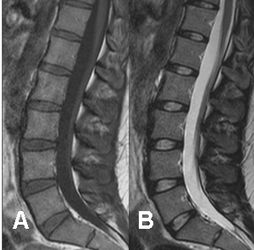

Fig 8. Medula ósea roja normal en adulto.

A: RM sagital en T1 y B: RM sagital en T2. Medula con señal intermedia en ambas secuencias.